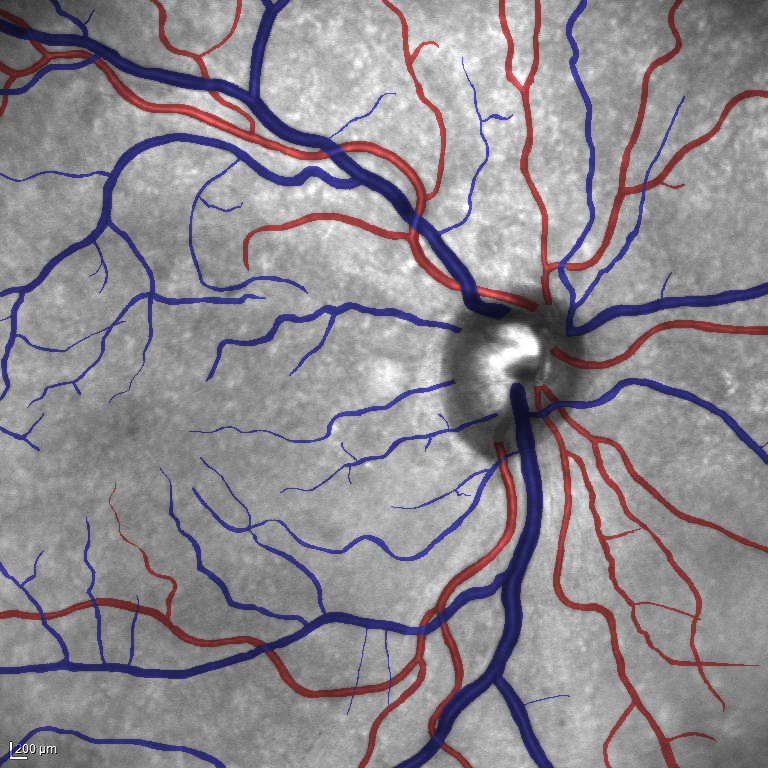

Table V presents quantitative performance benchmarks of SegRAVIR and other competing approaches for retinal artery and vein classification on the RITE dataset [11]. SegRAVIR outperforms previous state-of-the-art approaches in terms of accuracy, sensitivity, and specificity. Fig. 5 provides a qualitative comparison between segmentation outputs of SegRAVIR and the method of Hemelings et al. [40] on the RITE test set.

Using the final pretrained student SegRAVIR model in our knowledge distillation framework described in Section IV-D, we fine-tuned and tested the network on three publicly available datasets of color images, DRIVE [10], STARE [9], and CHASE_DB1 [12]. Fig. 7 shows example of SegRAVIR segmentation outputs on DRIVE and CHASE_DB1 datasets. Table VII presents a quantitative comparison between the segmentation performance of our SegRAVIR model and state-of-the-art models: R2U-Net [25], DU-Net [26], and IterNet [34]. By all evaluation metrics, SegRAVIR has achieved new state-of-the-art results on the DRIVE, STARE [9], and CHASE_DB1 datasets.